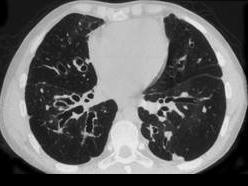

问题 男,18岁,咳嗽,咳痰,咯血半月余,CT检查如图,选出最可能的诊断 ( )

选项 A、大叶性肺炎 B、肺癌 C、支气管扩张 D、原发性肺结核 E、过敏性肺炎

答案 C